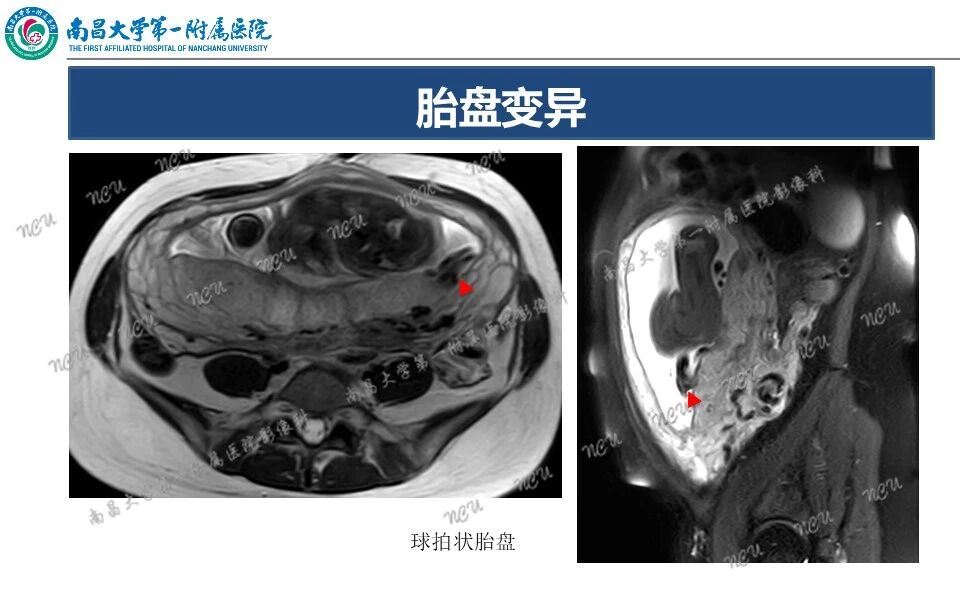

胎盘解剖及相关病变的MRI诊断